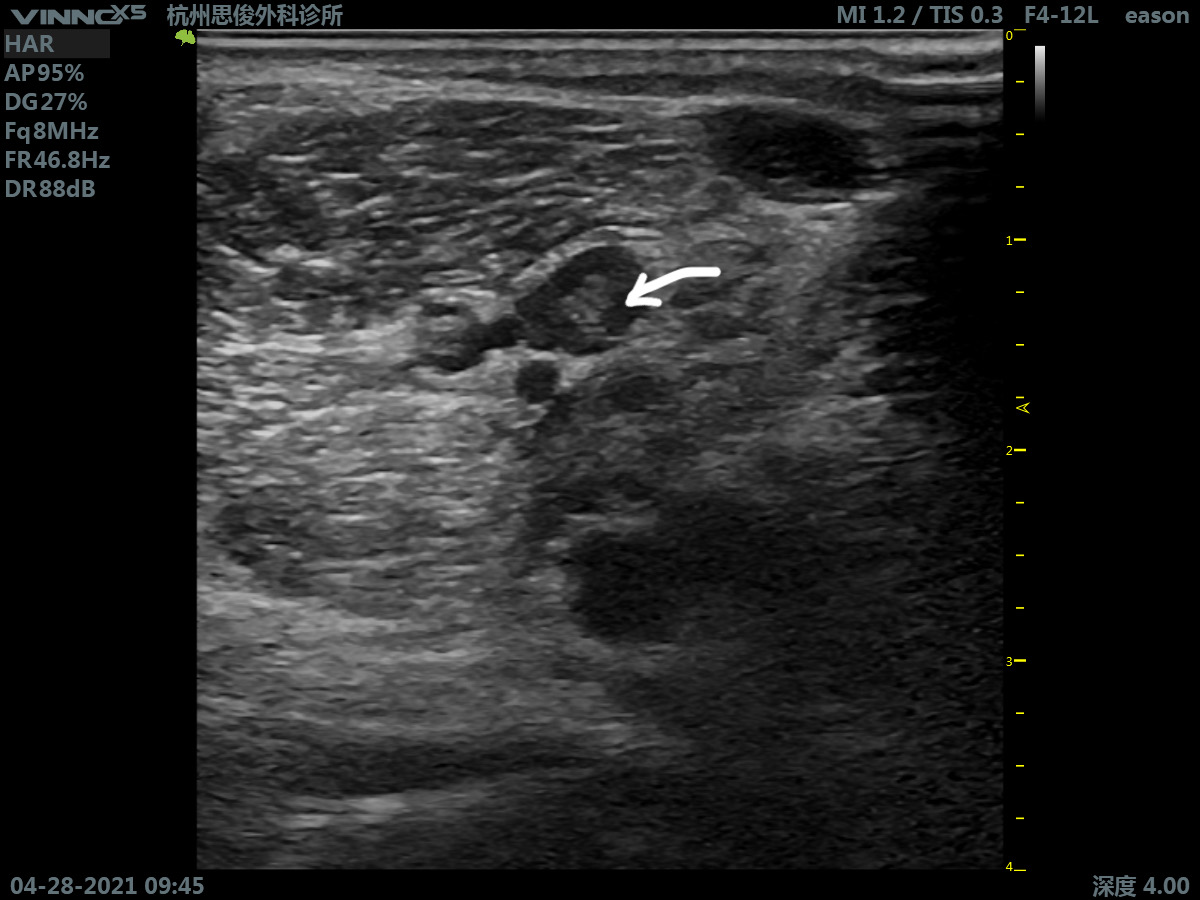

超声筛查发现患者右侧股静脉、膕静脉、腓肠肌内侧静脉内均有混合回声影填充且无法完全压闭,与之前(2019年)在当地医院超声看到陈旧性血栓的部位基本吻合。

回到病例 ,仔细辨别还可以发现:股静脉内呈高回声影,但是管腔可以被部分闭闭,而膕静脉和腓肠肌内侧静脉腔内呈低回声填充,血管扩张,管腔完全不能压闭。患者急查D-二聚体明显升高,结合其临床症状,判断其深静脉血栓复发,复发部分在膕静脉和腓肠肌内侧静脉内。